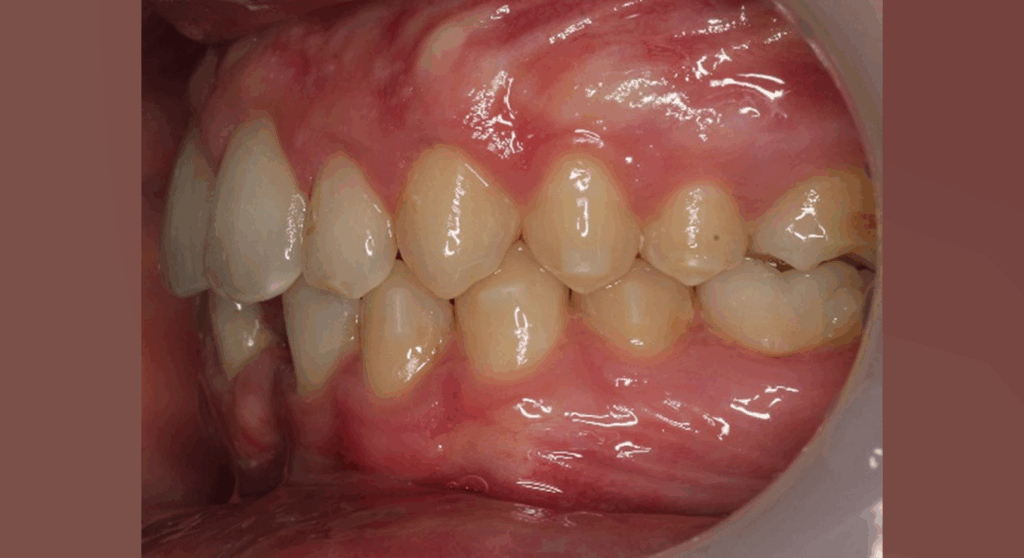

After 6 months:

Overjet reduced from 9 mm → 4 mm

Clear improvement in labial competence, nasal breathing, and tongue function.